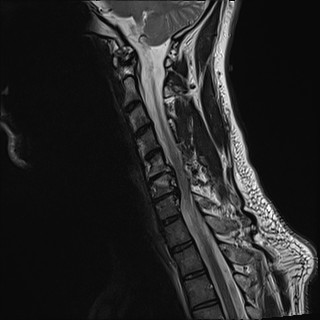

Wirbelsäule HWS

t2_tse_sag